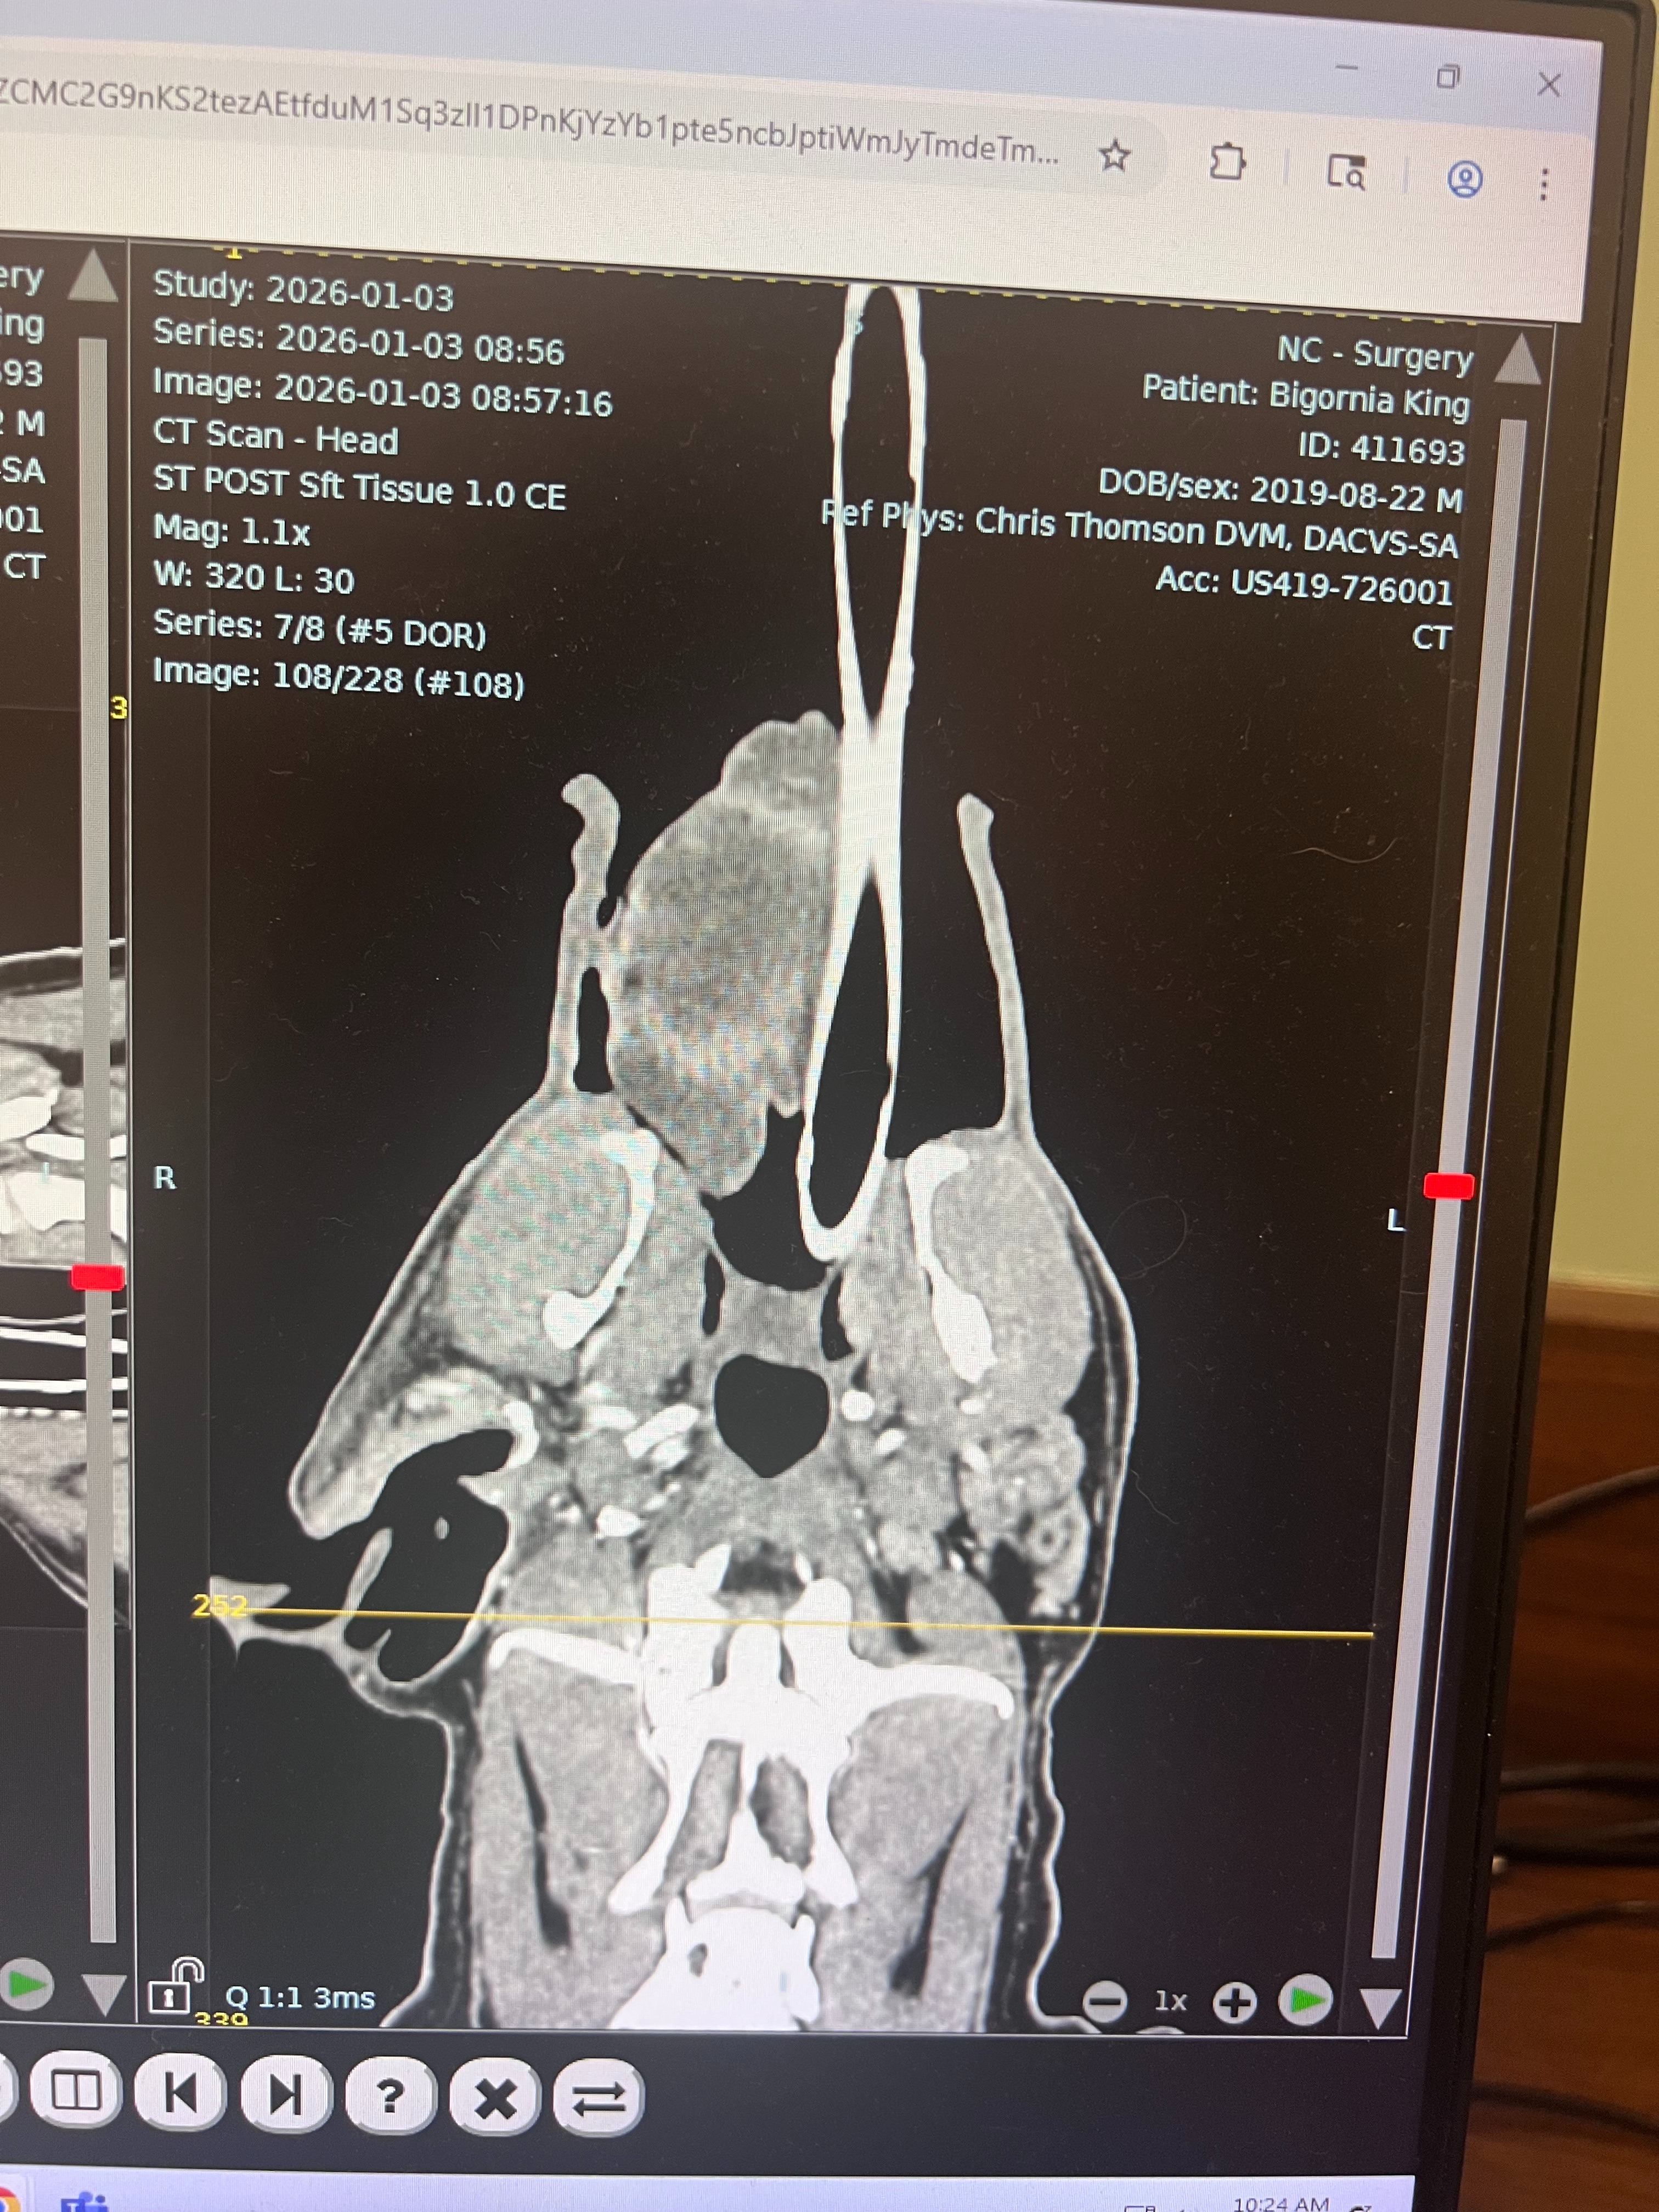

A CT scan was performed this morning, and there are 3 areas of concern: his ear has a large fluid-filled mass, his tongue has a large fluid-filled mass, and he also has a mass on his muzzle. The top rule-outs at this point are autoimmune disease, bacterial infection, or a fungal infection.